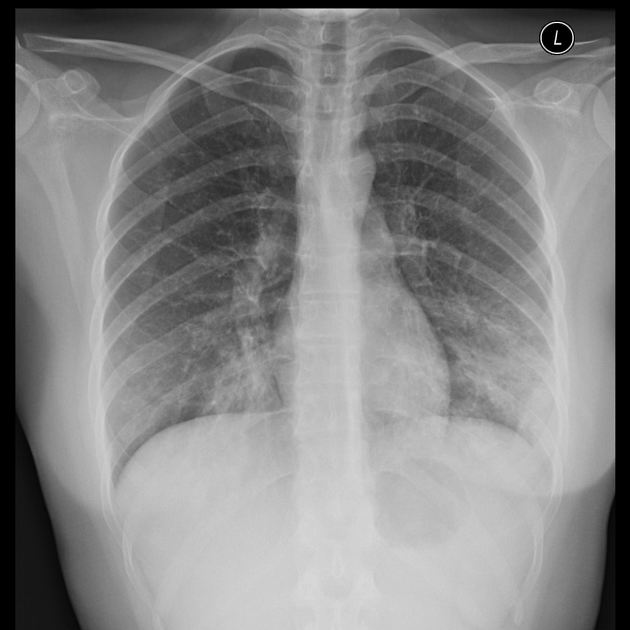

A 24-year-old woman, otherwise healthy, presents with a non-productive cough, sore throat, and myalgia. The patient reports that her symptoms started gradually 2 weeks ago and have not improved. She has no significant past medical history and no current medications. She is a college student and denies any recent overseas travel. The patient received the flu vaccine this year, and her 2-part PPD required for school was negative. She does not smoke, drink, or use recreational drugs. The patient denies being sexually active. The vital signs include: temperature 37.0°C (98.6°F), blood pressure 110/75 mm Hg, pulse 98/min, respirations 20/min, and oxygen saturation 99% on room air. On physical exam, the patient is alert and cooperative. The cardiac exam is normal. There are rales present bilaterally over both lung fields. The skin and conjunctiva are pale. The laboratory tests are pending. The chest X-ray is shown in the image. Which of the following laboratory findings would also commonly be found in this patient?